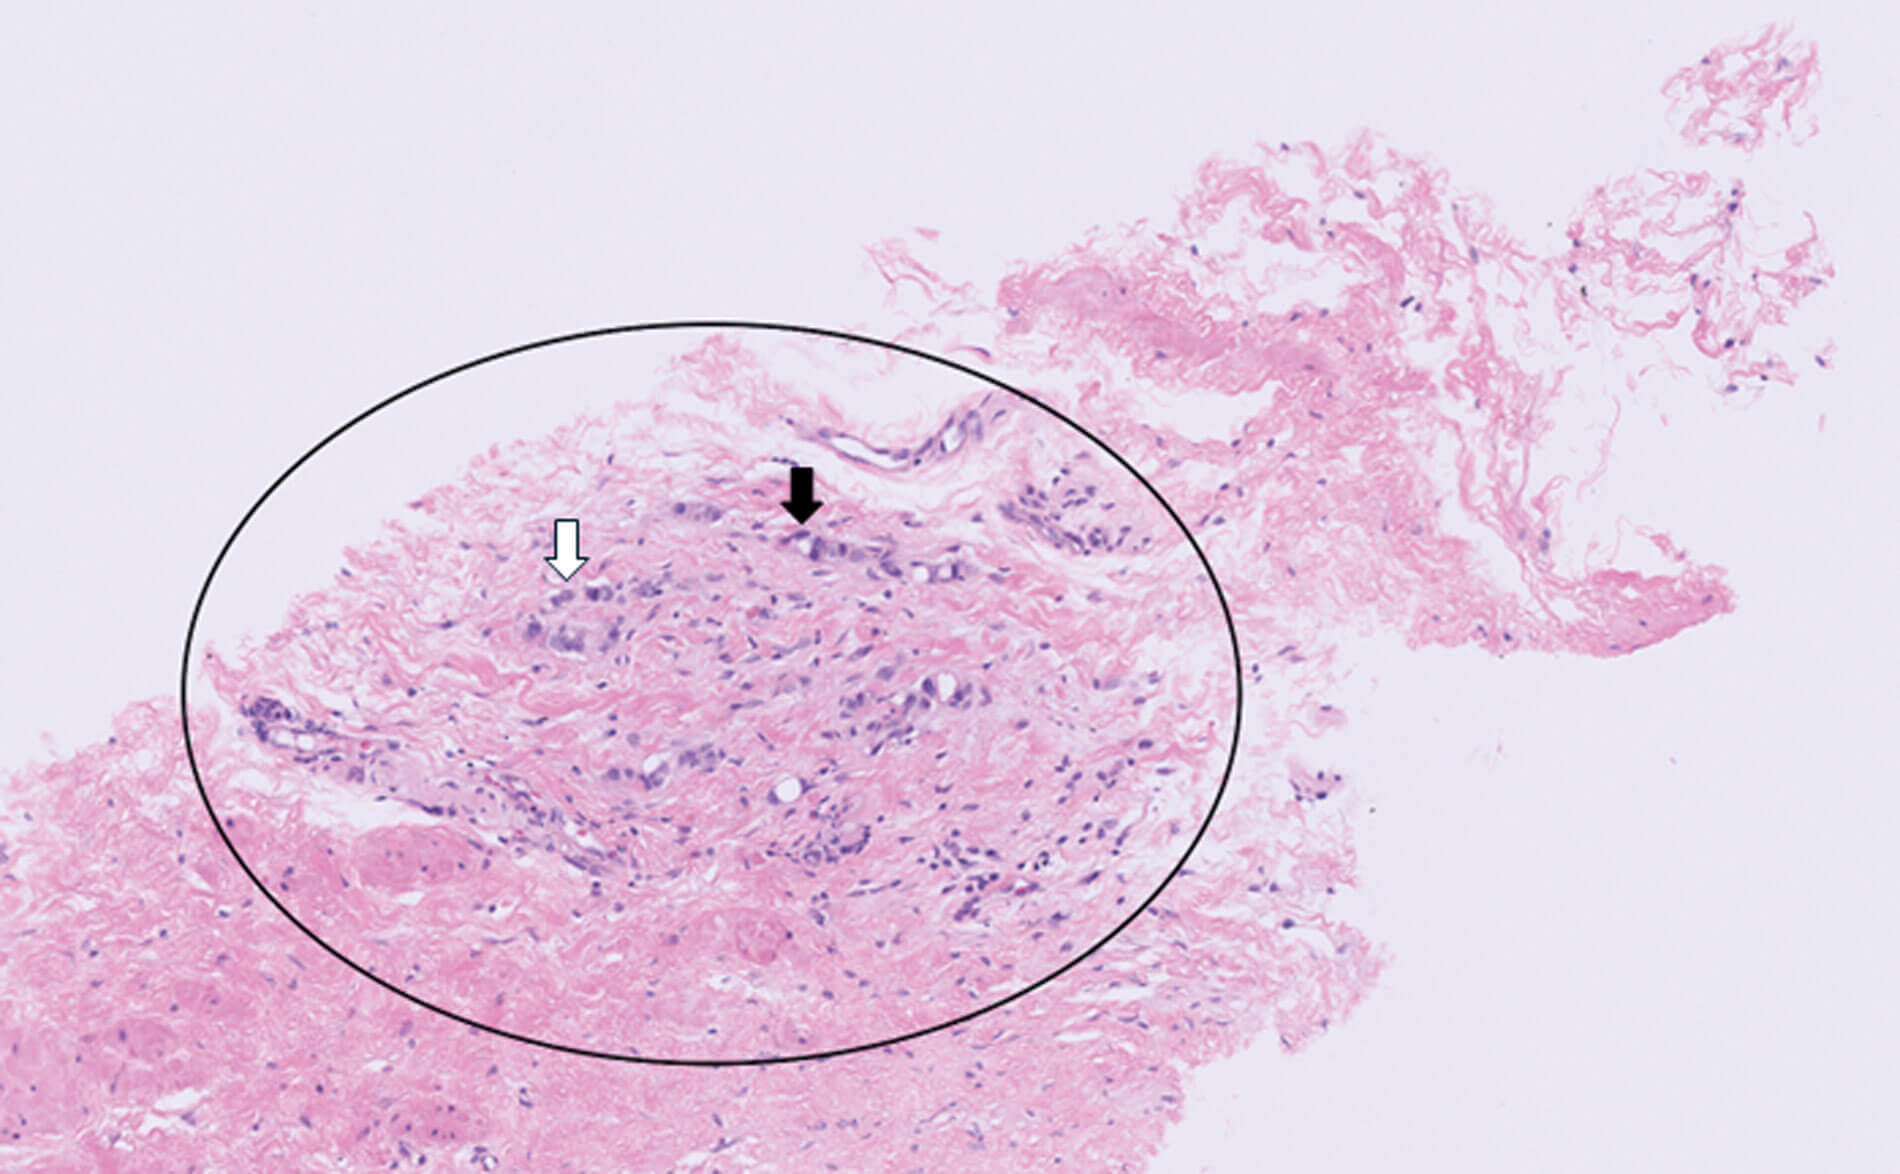

Figure 5.

2. Figure 5 shows a haematoxylin and eosin core biopsy of the prostate. Adenocarcinoma of the prostate is highlighted within the circle on the image, with single cords and poorly formed glands lacking a basal cell layer. This contrasts with benign prostatic acini which consist of a luminal cell layer surrounded by a basal cell layer. At high power, the tumour cells are seen to be enlarged with variably sized and shaped (pleomorphic) nuclei and prominent nucleoli (white arrow). They are arranged predominantly in cords (black arrow) and show minimal glandular differentiation (intracytoplasmic vacuoles). This arrangement of tumour cells is classified as Gleason 5 growth pattern.